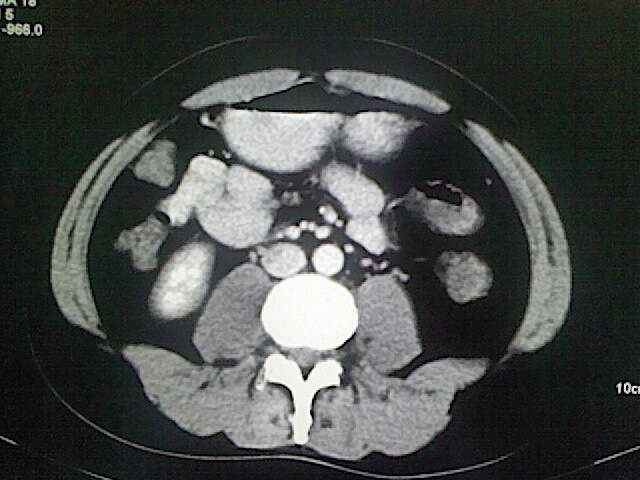

以下是引用卜一在2009-3-14 9:49:00的发言:[br]胆囊萎缩,胆囊壁不规则增厚,内部结构模糊,增强明显强化。另:肝左叶外侧段肝囊肿。支持:慢性胆囊炎!高度可疑:胆囊癌!

以下是引用余辉在2009-3-14 8:48:00的发言:[br]1)慢性胆囊炎。2)肝左叶外侧段肝囊肿。3)脂肪肝。[br]支持,胆囊萎缩,密度增高,不知b超具体有何提示,钙胆汁?结石?

以下是引用jiangjing在2009-3-14 10:18:00的发言:[br]1)慢性胆囊炎。2)肝左叶外侧段肝囊肿。3)脂肪肝。4.】建议行肝功能检查